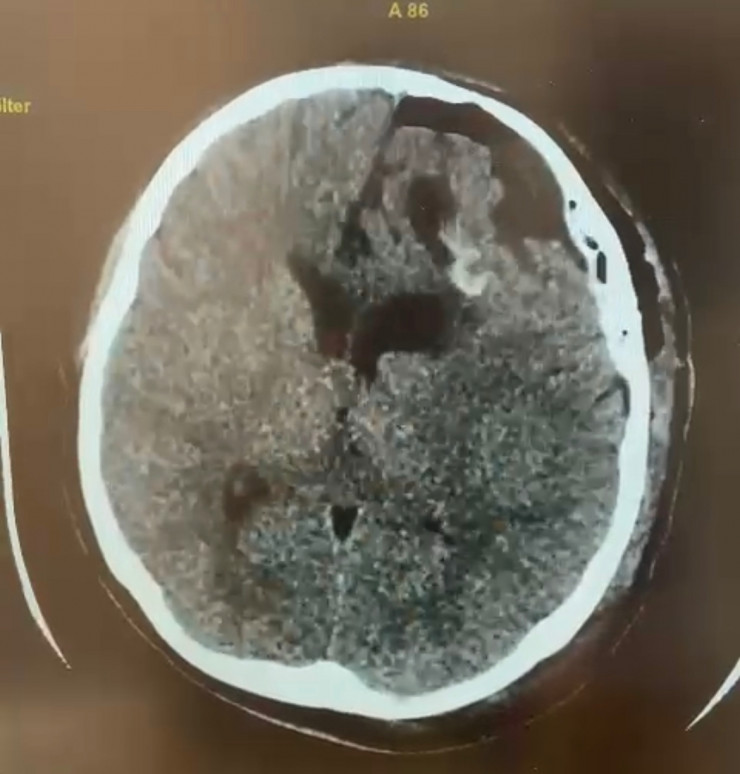

КТ-снимок после операции. Материал предоставлен общественным объединением KAZNEURO